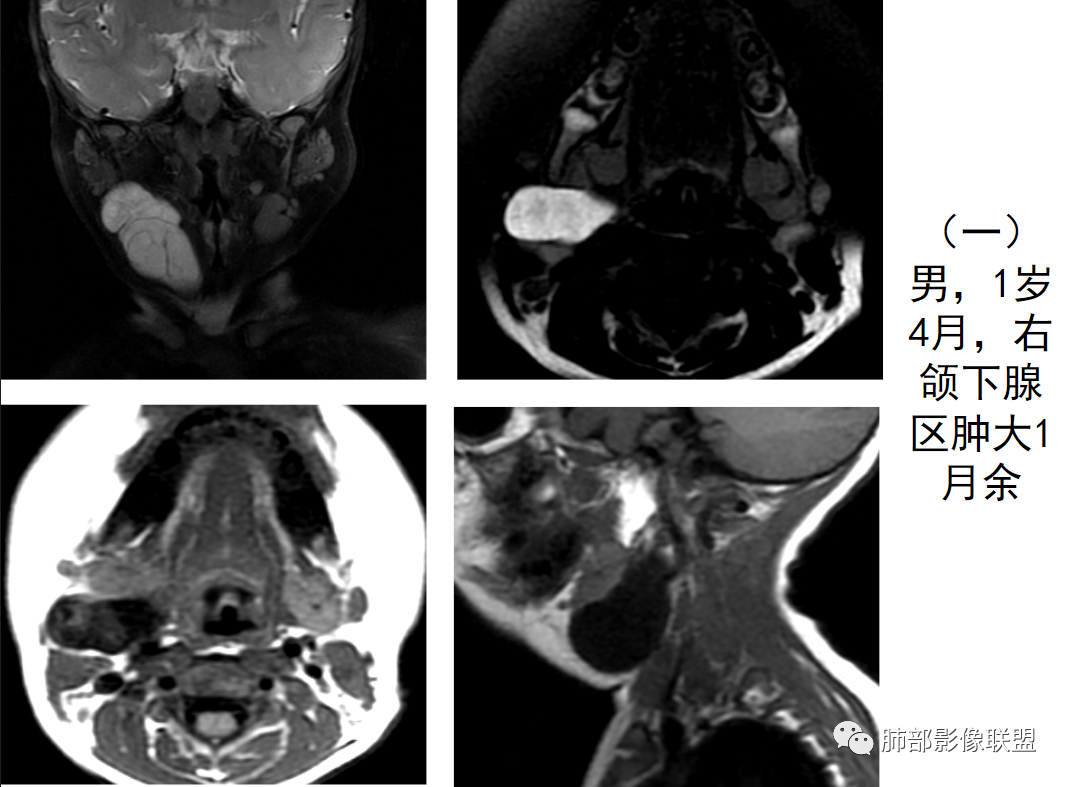

1958年由Vellios等首先报道,仅见于婴儿和年幼儿童,又称为胎儿脂肪瘤、胎儿脂肪肿瘤、胎儿细胞脂肪瘤、胚胎性脂肪瘤、先天性脂肪瘤样肿瘤不同于绝大多数的“母细胞瘤”,脂肪母细胞瘤是一种少见的幼儿软组织良性肿瘤,由不成熟脂肪细胞的异常增生形成。多发生于3岁以下儿童,约占80-90%,且男性多于女性,主要表现为无痛性肿块,有文献报道脂肪母细胞瘤发生于四肢的比例可达70%,下肢较上肢多见。也可见于头颈部、躯干、纵隔、腹膜后、肠系膜、骶尾部、阴囊、宫颈及心脏等处。该疾病的病因及发病机制尚不明确,许多文献认为可能是某些基因的突变所致,但目前尚无有力证据证明。其治疗以手术切除为主,预后较好,暂无恶变及转移的报道,但可复发。总体来说,对于其生物学行为的认识很重要,因为脂肪母细胞瘤的生物学行为属良性,应避免不必要的过度治疗。

脂肪母细胞瘤由成熟程度不同的脂肪组织、纤维间隔、黏液基质、小血管丛等间质成分组成,以脂肪组织与黏液样基质为主,其影像学表现取决于上述组织成分。典型的CT和MRI表现为:前后纵隔均可发生,常见于前纵隔;肿块大小不一,直径多在3cm~7cm,密度均匀,CT值呈水样或脂肪密度,脂肪组织密度或信号为主的肿块,其内密度或信号不均匀,可见粗细不一的分隔影,且有结节、片状影,后者可呈轻中度强化;结节状肿瘤包膜完整;弥漫性者包膜不明显,常呈浸润性生长;周围结构为受压和推移改变,可有少量胸腔积液,淋巴结无增大。

9、病例赏析